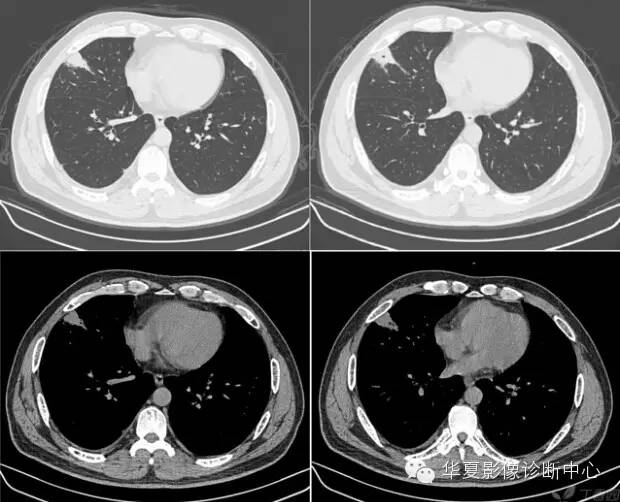

10、桃尖征 医学百科网 | YxBaike.Com

指肿块某一边缘尖角状突起形似桃尖,是肺炎性假瘤包膜的粘连牵拉,为良性肿块炎性假瘤特有。 医学百科网 | YxBaike.Com

医学百科网 | YxBaike.Com